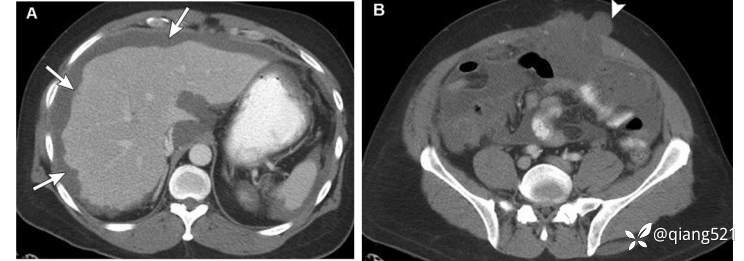

CT显示多灶低密度,实质脏器呈扇形压痕,典型表现在肝和脾表面,可有曲线状的钙化灶。然而,没有发现实质或内脏器官的直接浸润。这些发现值得仔细评估任何原发性阑尾肿瘤或卵巢肿瘤。

一例59岁男性阑尾粘液囊腺瘤破裂后腹膜假性粘液瘤。轴向CECT图像显示肝缘胶状黏液形成扇形压迹(箭头A),并延伸至腹壁切口疝(箭头B)。